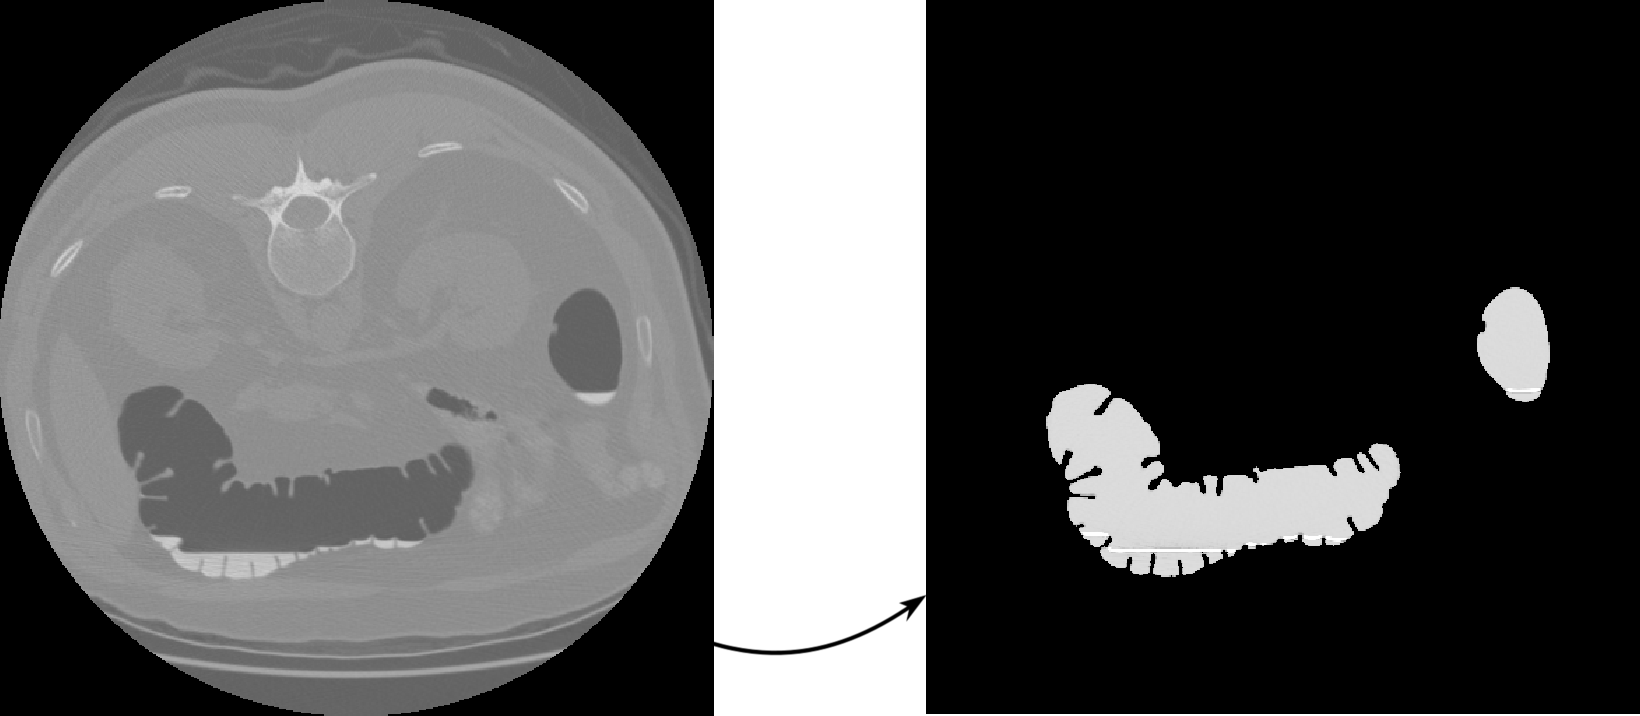

II-A Classifying CT regions

All the cases from the used database have the same preparation, which includes solid-stool tagging and opacification of luminal fluid, and can be noticed as the white liquid in Figure 2. One of the strongest difficulties concerning the segmentation of the colon from abdominal volumes in CT is the presence of this tagged fluid and its interfaces with air and tissue. Figure 2 shows a CT slice and its pixel values over the highlighted vertical profile. At first sight there are three clearly distinguishable classes: the lowest gray levels correspond to air, the highest levels correspond to fluid, and the middle gray values correspond to tissue. Nevertheless, there are around interface voxels between air and fluid whose gray values, due to continuity, lie within the normal tissue range. Therefore, a naïve approach based on gray values only, ignoring the physical nature of the tissue and its environment, is not suitable for proper tissue classification and segmentation.

Figure 3 shows a slice of the original volume data and the same slice of the initial segmentation .